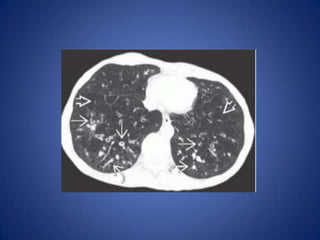

– CT

• Bronchial abnormalities clearly shown

• Diffuse low attenuation and small vessels often present

in parenchyma supplied by dilated and inflamed

bronchi

• Extensive air-trapping may be apparent on expiratory

CT